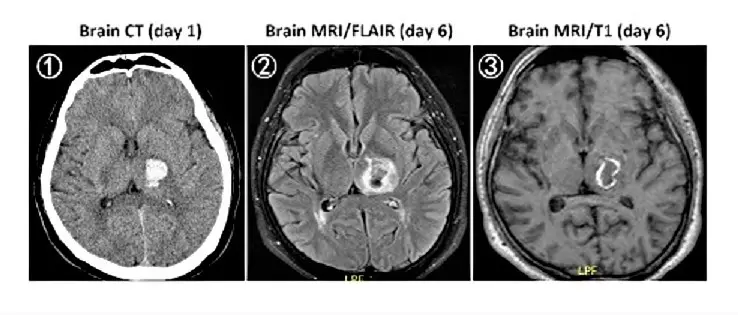

49歲男性平常有高血壓,因突發性右側肢體無力及麻木而就診,就診當天的無顯影劑腦部電腦斷層( non-contrast CT)檢查結果如下圖①, 5 天後的腦部磁振造影( MRI )檢查結果如下圖②( Fluid attenuated inversion recovery, FLAIR)及圖③無施打顯影劑之 T1 影像。下列何者最有可能是此病人的診斷?

圖①(day 1,Non-contrast CT):

• 左側基底核區可見一約3–4公分之高密度病灶,相對周圍正常腦組織呈現明顯高吸收(80–100 HU vs. 40–50 HU),邊緣較銳利,內部密度均一,並有輕微質量效應使同側側腦室及皮質溝受壓移位。

• 依據CT急性期血腫特徵,高蛋白血紅素含量使血塊呈高密度(acute ICH <3 days hyperdense)(clinicalpub.com)。

圖②(day 6,FLAIR MRI):

• 病灶中心呈相對低信號(deoxyhemoglobin或早期methemoglobin造成T2縮短),周邊環狀高信號(vasogenic edema及部分methemoglobin造成T2延長)。

• 出血於第3–14天之間為亞急性期,影像信號可自周邊向中心退化,且FLAIR對血腦屏障外之血腦濾液及細胞間水增多敏感,呈高信號([clinicalp